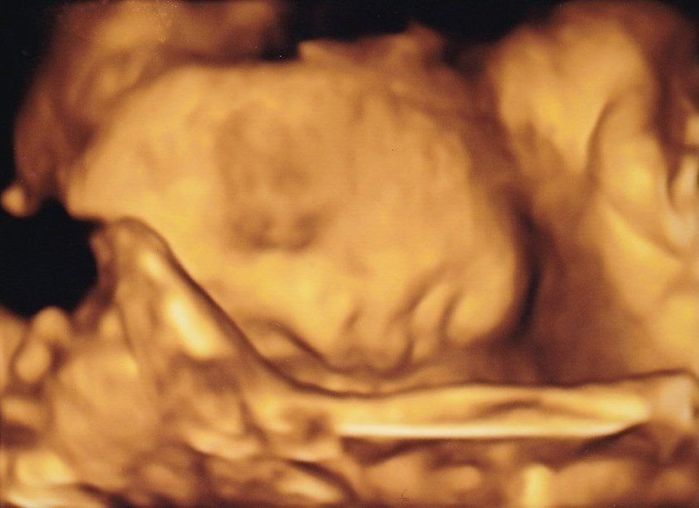

妊娠24週目の4Dエコー写真 顔の表情がわかり、少しだけ親近感が湧く

推定体重=854g

お顔のアップの4D画像です。手を顔の前においてこちらを見ていて、少し心配そうなお顔に見えました。おなかの中でぽこぽこしたり、ぐるぐるしたりする感覚がありましたが、いまいち胎動なのかはわからず、「あ、動いた」と感じるような胎動に感動することがないまま日々が過ぎました。アイスクリームとチョコレートが大好きになり、我慢するのがつらかったです。